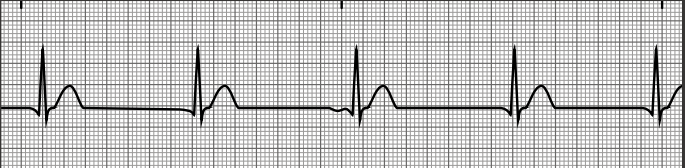

first-degree heart block (1)

second-degree heart block type II

second-degree heart block type I

third-degree heart block

first-degree heart block (2)